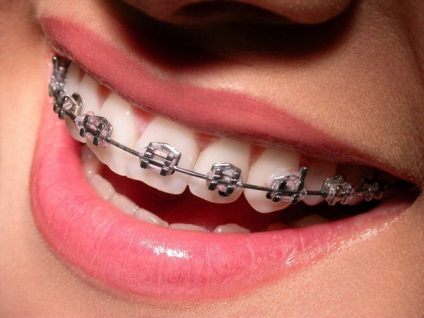

Ők vannak rögzítve a fogat. A képen fent bemutatott, akkor láthatjuk, hogyan néz ki szerelt konzol. Ők alapították a saját információit szögek, hiszen még a felső és az alsó metszőfogak más adat. Hogy a zárójelben - a fáradságos, sőt azt mondhatjuk, ékszer munkát. Az anyag, amelyből készült, különböző lehet, ami azt jelenti, hogy négy féle kapocs:

- Vestibular. Ahhoz, hogy a külső oldalon az egyes fogak kapcsolódik speciális ragasztóval kopozitivnogo csattal. Keverjük össze a sorrendet nem lehet, mert ez vezethet szövődmények. Miután minden egyes meghatározott elem menetes ív teljesítmény. Ez egy vezeték, amely információkat hordoz a helyzetben a fogszabályozó. Ez történt a rugalmas és elasztikus anyagok. Tekintettel a telepített rendszer is látható a képen.

Malocclusion - egy nehéz és hosszú távú kezelés, melynek költsége elég magas. Fém fogszabályozó betegek választja gyakrabban mint más típusok. A lényeg az, hogy ez a rendszer a nagy szilárdság és lehetővé teszi, hogy javítsa ki a harapás, amint az a fenti képen, hogy rövid idő alatt. Vélemények a fém merevítők pozitív. Annak ellenére, hogy a kényelmetlenséget fogszabályozó viselése és csúnya, olyanok, mint a legtöbb beteg.